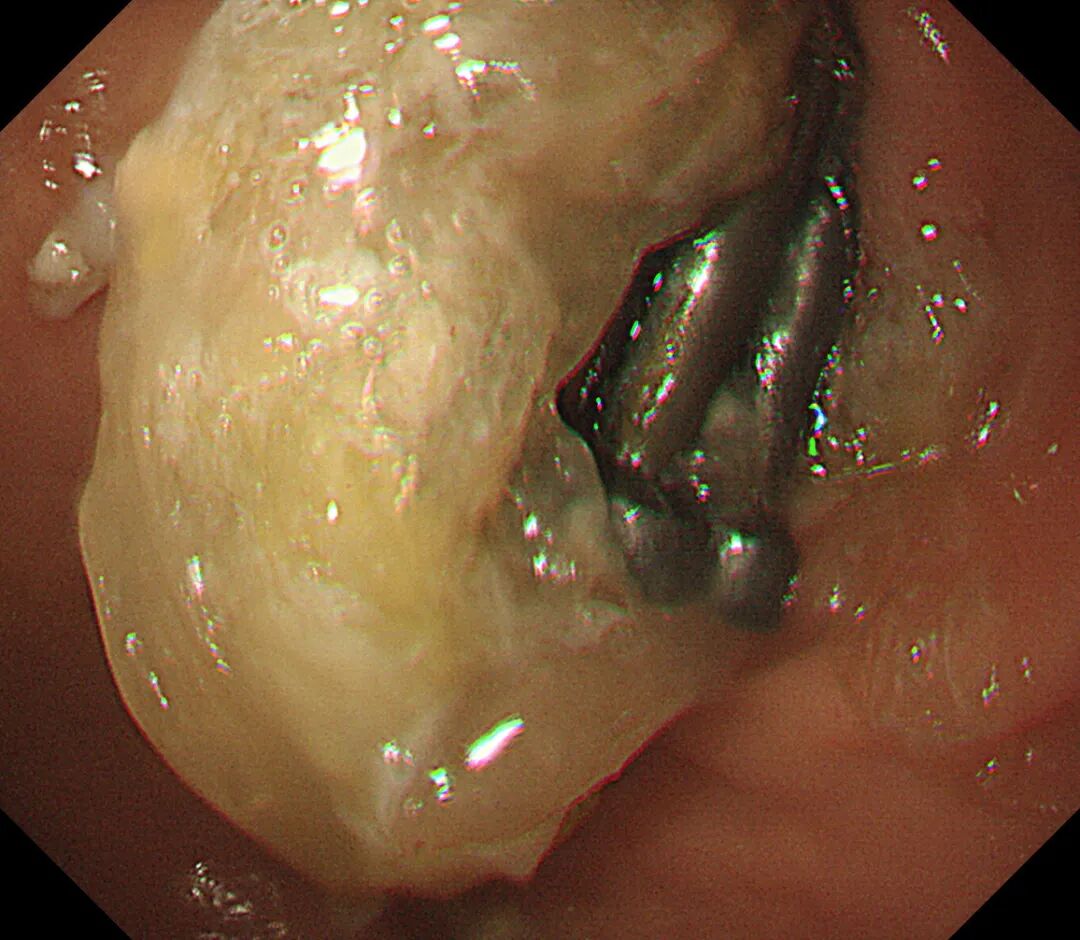

如何将风险降到最低,宜宾市中医医院立即开通绿色通道,多科协作,经讨论决定选择对娃娃损伤最小的全麻下经胃镜行消化道异物取出术。术中在胃镜下见4枚铁钉嵌顿于幽门口,随时有排入十二指肠的风险,立即予异物钳夹取,整个操作过程娴熟、流畅,成功将4枚铁钉完整取出。

正当大家觉得松了一口气时,胃镜再次进镜复查,在十二指肠降段处又发现5枚铁钉,此处是胃镜所能到达的最远距离,一次正常的肠蠕动或者细微的操作都有可能导致铁钉滑入十二指肠远端,胃镜将无能为力,此刻手术室气氛再次变得凝重。

但是如何将5枚4公分长的铁钉通过近乎直角的十二指肠球降交界转角处,以及再从狭小的幽门口取出,成了又一大难题,面对不断出现的困难,颜主任凭借多年的内镜经验,及时调整圈套器夹取铁钉的距离和方向,改变铁钉与腔道的角度,顺利将5枚铁钉拉到胃内,并将其全部取出体外,为确保患儿体内已无铁钉,急诊行床旁腹部摄片检查,结果提示患儿腹部未查见高密度金属影,宣告所有铁钉已全部取出,顿时整个手术室一片欢呼。